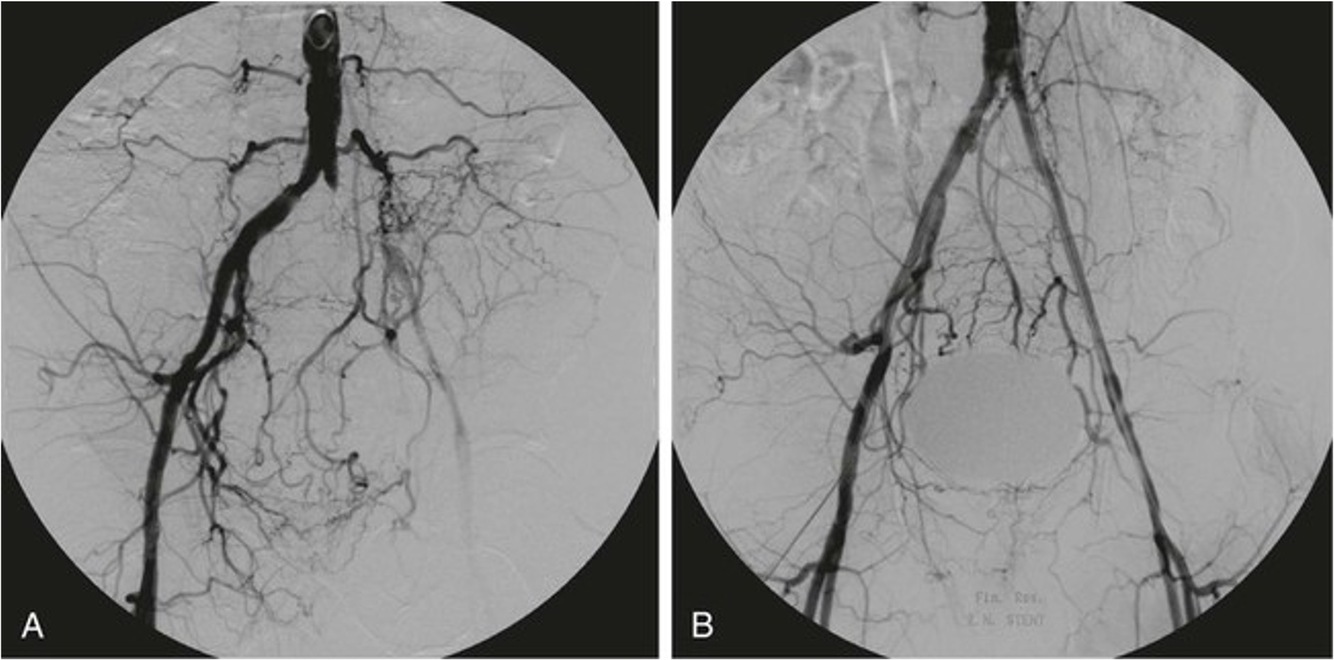

Digital subtraction angiography showing occlusion of left common iliac artery

Digital Subtraction Angiogram Left leg demonstrating occlustion of the left SFA – reconstituting lower through collaterals